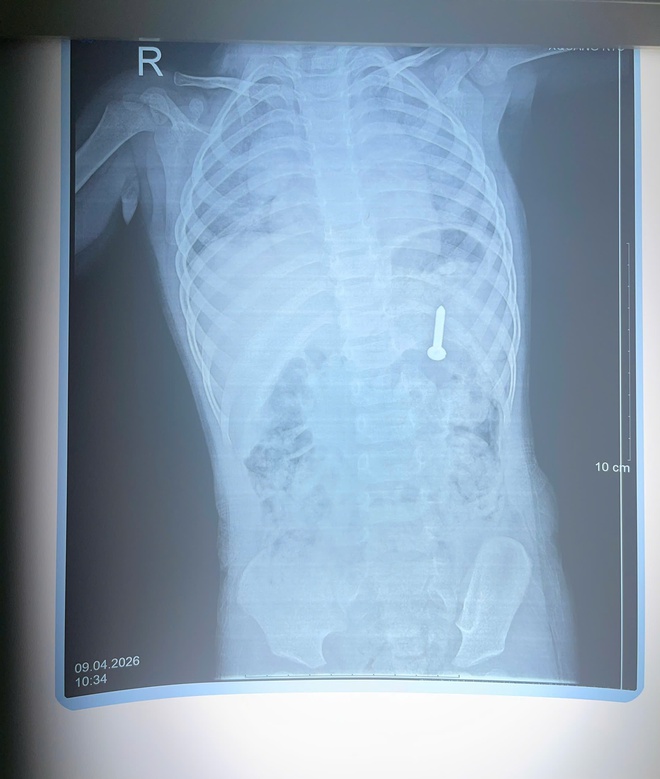

Dị vật đinh vít.

Qua thăm khám và chụp X-quang, các bác sĩ xác định dị vật nằm trong dạ dày. Nếu không được xử lý kịp thời, dị vật có thể gây thủng đường tiêu hóa, xuất huyết và nhiều biến chứng nguy hiểm.